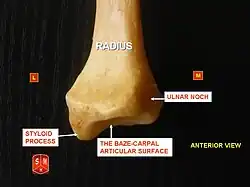

Radius, styloid process - anterior view

Radius, styloid process - anterior view -

Radius, ulnar notch - posterior view

Radius, ulnar notch - posterior view -

The distal end of the radius is large and of quadrilateral form.

It is provided with two articular surfaces – one below, for the carpus, and another at the medial side, for the ulna.

- The carpal articular surface is triangular, concave, smooth, and divided by a slight antero-posterior ridge into two parts. Of these, the lateral, triangular, articulates with the scaphoid bone; the medial, quadrilateral, with the lunate bone.

- The articular surface for the ulna is called the ulnar notch (sigmoid cavity) of the radius; it is narrow, concave, smooth, and articulates with the head of the ulna.

These two articular surfaces are separated by a prominent ridge, to which the base of the triangular articular disk is attached; this disk separates the wrist-joint from the distal radioulnar articulation.

- The lateral surface is prolonged obliquely downward into a strong, conical projection, the styloid process, which gives attachment by its base to the tendon of the brachioradialis, and by its apex to the radial collateral ligament of wrist joint. The lateral surface of this process is marked by a flat groove, for the tendons of the abductor pollicis longus muscle and extensor pollicis brevis muscle.